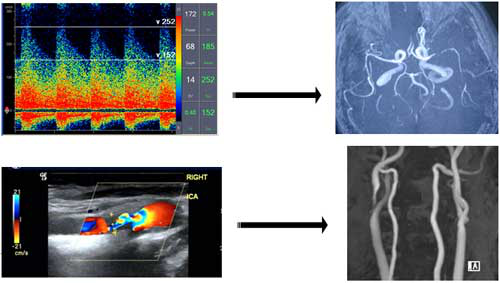

需要说明的是虽然部分后循环缺血会引起孤立性眩晕的症状,但绝大部分的不伴有脑部症状的孤立性眩晕并不是脑梗死所致。尤其需要注意的是,颈部血管超声、TCD等检查提示的“血管狭窄、椎基底动脉供血不足”等检查结果,并不是诊断后循环缺血的依据,而且在正常人群中约

15%的人存在一侧椎动脉变细现象。因此,可以这样说,临床绝大部分眩晕发作与脑血流无关,而且“脑供血不足”这个诊断目前已被医学界废除。所以,请您不必因一份这样的TCD或颈部血管超声的报告而过分担忧。如我们考虑存在后循环缺血的可能性,我们将会根据需要为您预约头颅MRI检查。

脑血流图不能成为诊断眩晕疾病的标